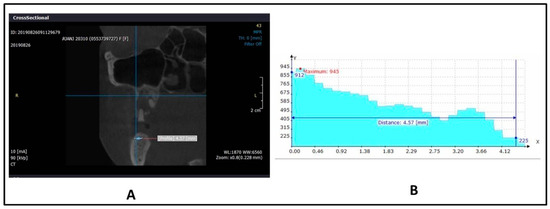

After being included in this inquiry; each participant was thoroughly evaluated to gather updated information regarding their medical and dental histories, complaints, and demographic data, including, age, gender, education, marital status, occupation, and, address. Moreover, the participants were clinically examined by a well-trained oral surgeon and prosthodontist following previous investigations [30,31,32,33,34]. A dental mirror (15/16 inch; Hahnenkratt, Königsbach-Stein, Germany) and a dental explorer probe (0700-9, anatomical handle single ended; ASA Dental, Bozzano, Italy) were used during the clinical examination of each participant on a dental unit. A CBCT (Index test) radiograph (SORDEX, Nahkelantie 160 Tuusula, Finland) was taken for the upper and the lower jaws of each participant, in order to check for local problems, to help during implant treatment planning [35], and to measure Hounsfield values of jaw bone density (machine settings: Medium field of view, 0.2mm voxel size,90KV). Then, the GS values were calculated for each participant using the CBCT radiograph and associated computer software, using OnDemand 3D, Yuseong-gu, Daejeon, Korea (Figure 1). For each participant, the GS values were calculated at four regions; namely, anterior maxilla, posterior maxilla, anterior mandible, and posterior mandible. After that, each participant was requested to provide the investigator with documentation of the results of the reference test (DXA values) they had for screening, or the diagnosis of osteoporosis by medical professionals, as it allows high resolution images, precise short time scanning, and the stability of calibration (Figure 2) [3]. The T value information from the reference test was not available to the performers of the index test, but the same was provided to a statistician directly, as submitted by each participant who underwent the reference test. The assessors of the reference test were also not aware of the clinical presentation and GS values of the participants. For all participants, the assessment of GS was performed by one investigator (MGS). Intra-examiner reliability was confirmed by the recalculation of 10 duplicate GS evaluations by the same investigator (MGS) (Kappa was 0.89–0.95). Moreover, inter-examiner reliability was confirmed by recalculation of the same 10 GS evaluations by another investigator (MKA) (Kappa was 0.85–0.92), which is considered satisfactory [36,37,38].

Figure 1. (A): Measurement of grayscale (GS) values using cone beam computed tomography (CBCT) technique in maxilla. (B): Graphical representation of corresponding GS value (HU).